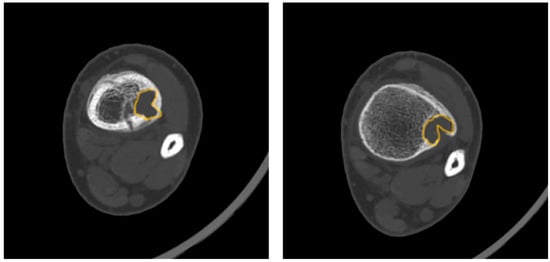

- Pac-Man Sign—Proliferation of bone anterior and posterior to the syndesmosis results in a shape that resembles the video game character “Pac-Man”. This sign was found to be highly specific (95%) but not very sensitive (47%) for predicting pathologic fracture (Figure 3).

- Syndesmosis Sign—Advanced imaging shows the syndesmosis inserting into the distal tibia lesion. This sign was found to be highly sensitive (94%) but less specific (48%) for predicting fracture risk.

- Computed Tomography (CT): CT can be useful for evaluating the degree of cortical thinning, which is important when assessing fracture risk [24]. CT is superior for delineating the precise cortical integrity. It allows for quantitative measurement of the cross-sectional area occupied by the lesion, which is a key factor in biomechanical models predicting fracture risk. The signs described above can also be visualized on a CT scan. Figure 3 demonstrates a “Pac-Man Sign” on CT of a 13-year-old boy who had a fracture through an NOF.